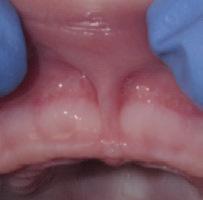

www.smilewonders.com

EDUCATION: Harvard School of Dental Medicine

EXPERTISE: Dr. Jaju is the only pediatric dentist in the MidAtlantic region who has achieved Advanced Laser Proficiency Certification from the Academy of Laser Dentistry and Breastfeeding Specialist Certification.

“During National Children’s Dental Health Month, and every month throughout the year, we want to stress the importance of taking care of your children’s teeth and oral health from the very beginning,” said Dr. Rishita Jaju, owner of Smile Wonders in Reston, Virginia and a board certified

pediatric dentist. “This helps develop healthy habits young so your children will become healthy adults.”

While we won’t say no to all sugars, there are things we can do to help prevent the negatives effects of sugar on young teeth.

1. Brush and Floss Regularly

Brush your child’s teeth or have them brush twice a day with a fluoride toothpaste and a soft-bristled brush. Wait 30-60 minutes after eating sugar or acidic foods before brushing though; brushing too soon can erode softened enamel. Always have your children brush before going to bed because as we sleep our mouths are drier, and there is a risk they won’t make enough saliva to counteract the bacteria caused by sugar left in the mouth. Clean between the teeth daily with regularly flossing. For babies, wipe your child’s gums after each meal.

2. Rinse the Mouth

When you eat, the pH level in your mouth becomes more acidic, which is never good for tooth enamel. The acid can dissolve the minerals that make up the tooth enamel and leave areas vulnerable for bacteria. After eating sugary foods, have your child rinse out or swish their mouth with plain water to counteract the plaque acids.

3. Reduce Snacking

Limit your child’s snacking on sugary foods to short periods of time, rather than snacking throughout the day. This helps reduce acid production in the mouth and lets the saliva levels rebalance in between meals.

4. Eat Healthy Foods

Feed your children healthy foods and limit sugary beverages served with meals and in-between. Vegetables and fruits are important, along with good sources of calcium like milk, yoghurt and broccoli.

5. Get Regular Dental Checkups and Cleanings

Bring your children to their pediatric dentist for regular check-ups and professional cleanings at least twice a year. This will help remove plaque and tartar that just can’t be reached with brushing and flossing.

At Smile Wonders, we prioritize preventive care by creating positive experiences for children and informative visits for parents. Come find out why kids love us and parents trust us for their infants, toddlers and children with various levels of needs and abilities.

Dr.

571-350-3663

11790 Sunrise Valley Drive, Suite 105 Reston, VA 20191

Dr. Rishita Jaju was honored to be selected as a TedX speaker in November, 2023.